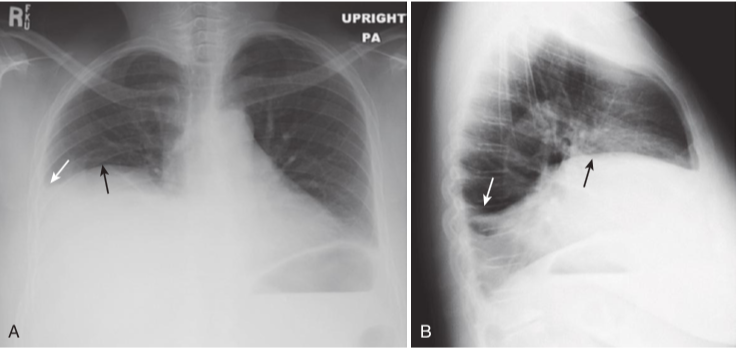

Meniscus sign, right pleural effusion.

A, On the frontal projection in the upright position, an effusion typically ascends more laterally (white arrow) than it does medially (black arrow) because of factors affecting the natural elastic recoil of the lung. B, On the lateral projection, the fluid ascends about the same amount anteriorly and posteriorly, forming a U-shaped density called the meniscus sign (white arrows).